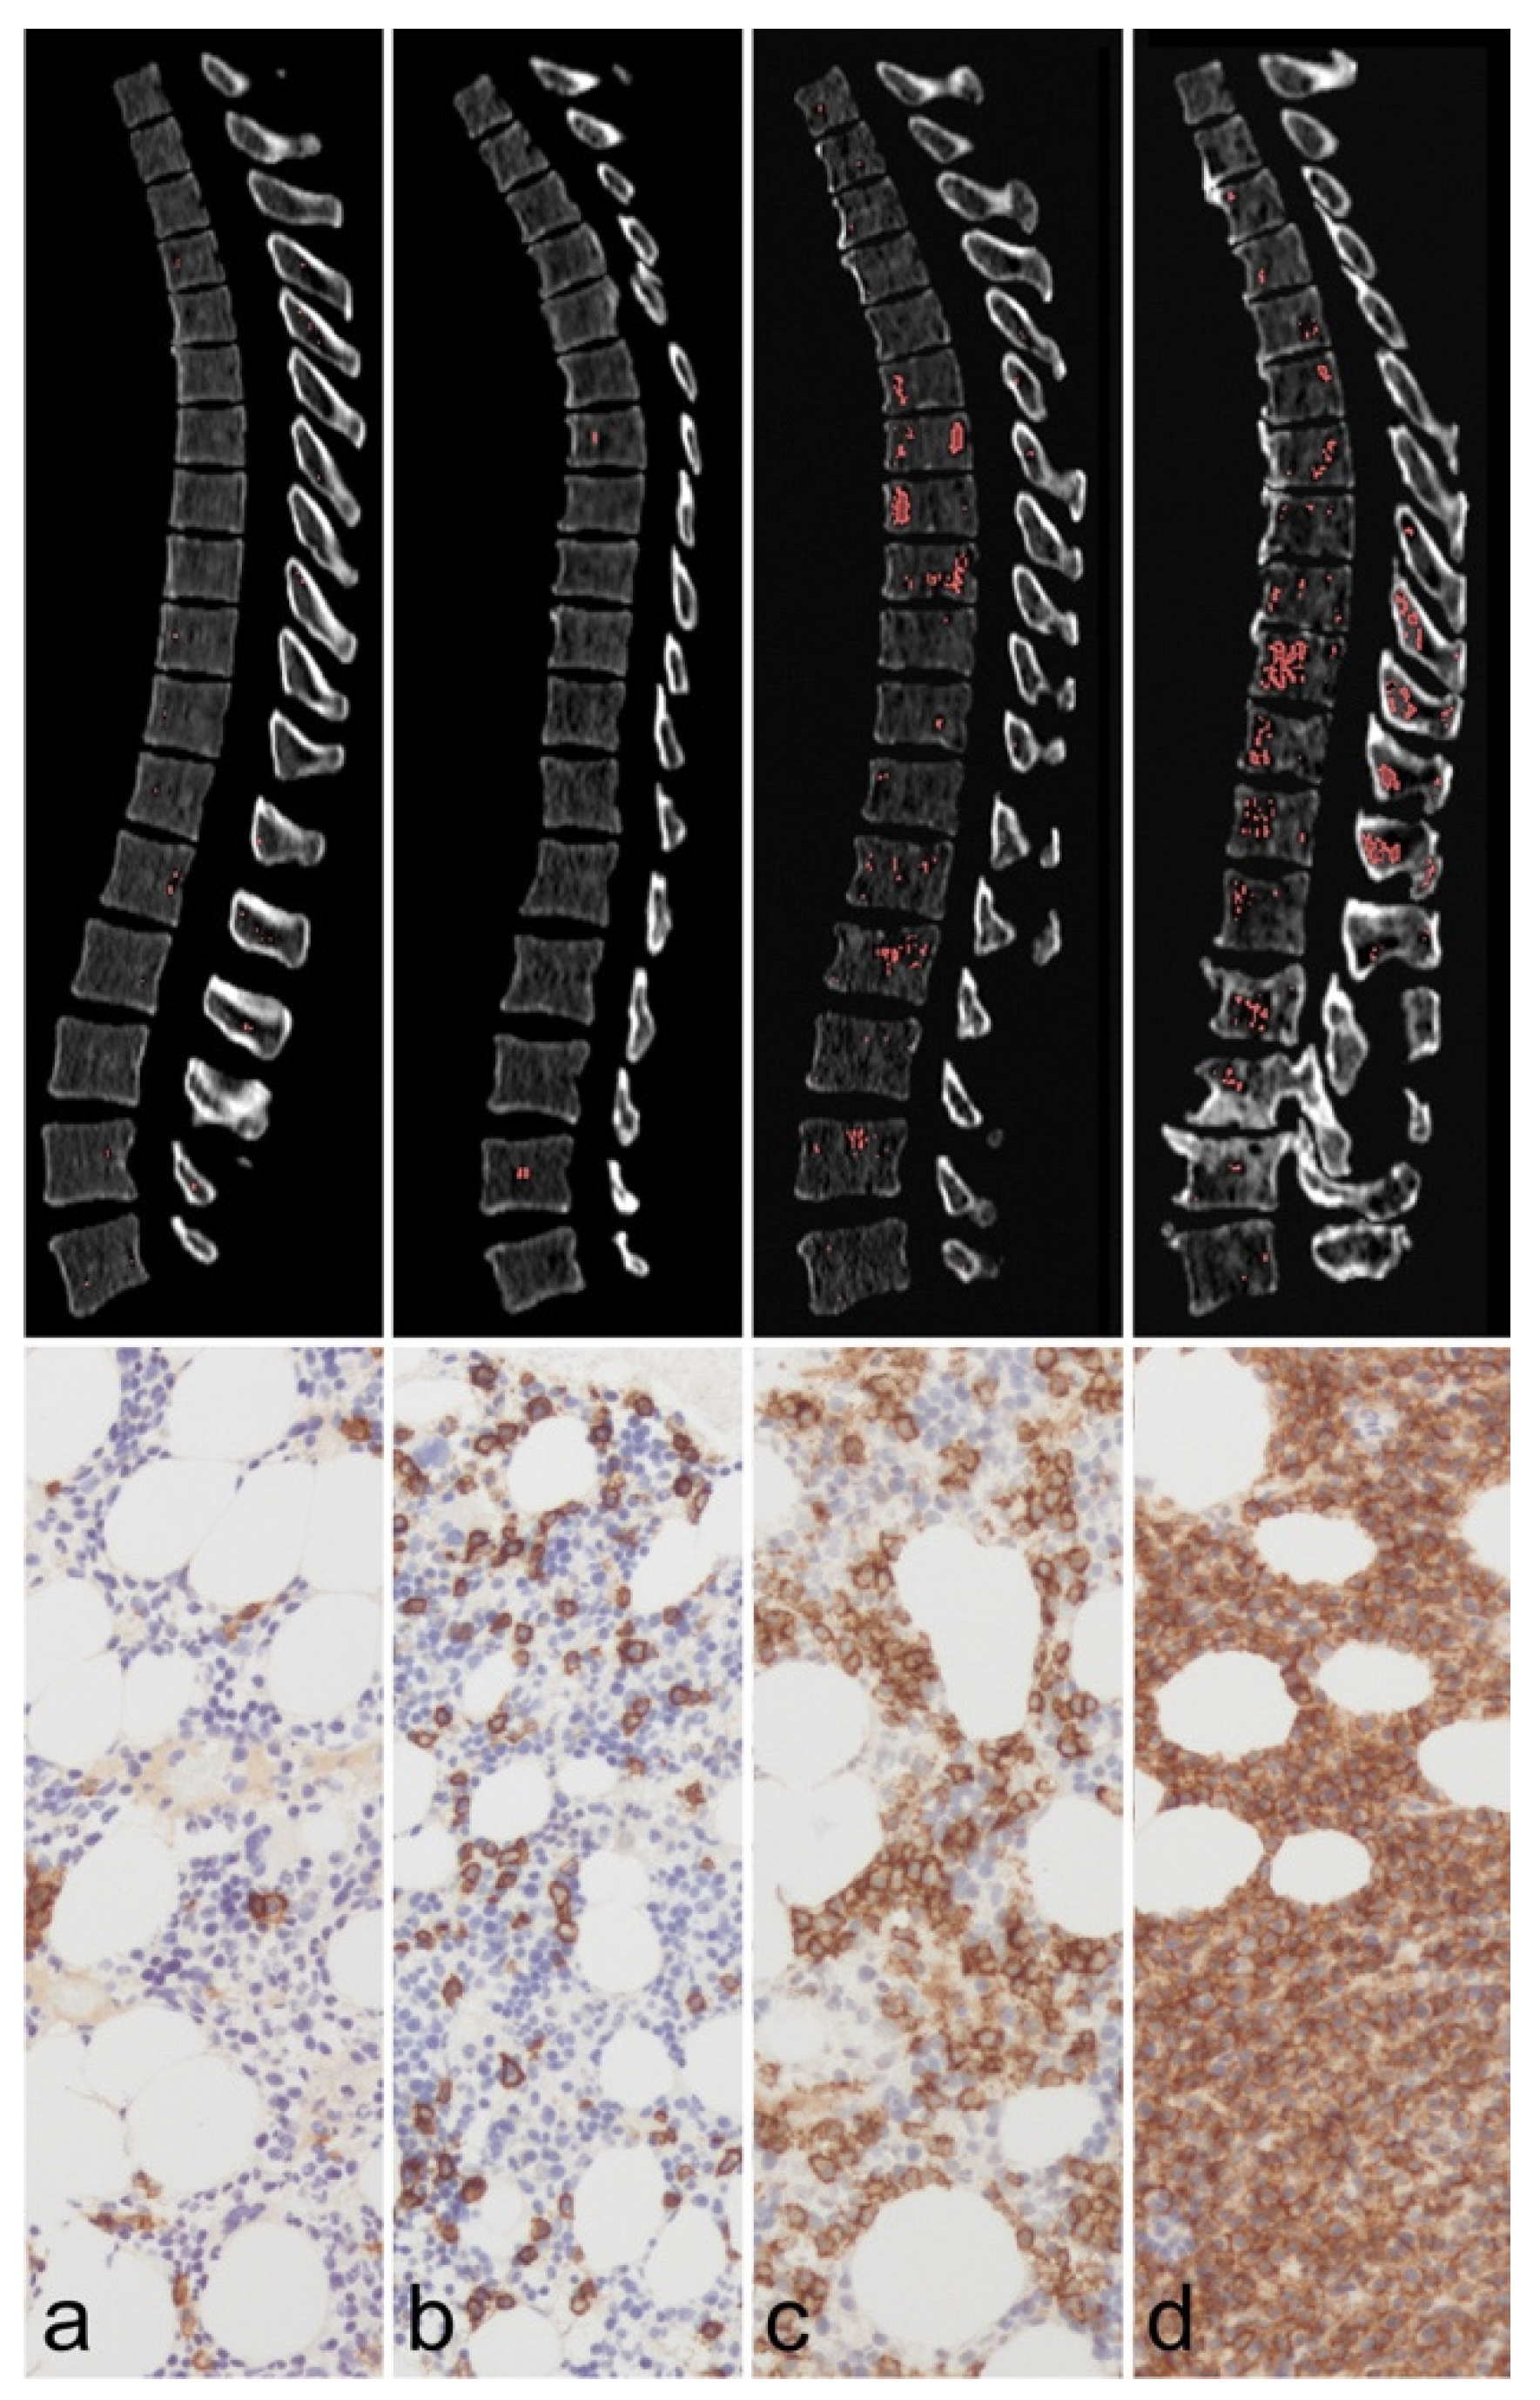

- Thomas, C.; Schabel, C.; Krauss, B.; Weisel, K.; Bongers, M.; Claussen, C.D.; Horger, M. Dual-energy CT: Virtual calcium subtraction for assessment of bone marrow involvement of the spine in multiple myeloma. AJR. Am. J. Roentgenol. 2015, 204, W324–W331. [Google Scholar] [CrossRef]

- Fervers, P.; Fervers, F.; Kottlors, J.; Lohneis, P.; Pollman-Schweckhorst, P.; Zaytoun, H.; Rinneburger, M.; Maintz, D.; Große Hokamp, N. Feasibility of artificial intelligence-supported assessment of bone marrow infiltration using dual-energy computed tomography in patients with evidence of monoclonal protein—A retrospective observational study. Eur. Radiol. 2022, 32, 2901–2911. [Google Scholar] [CrossRef] [PubMed]